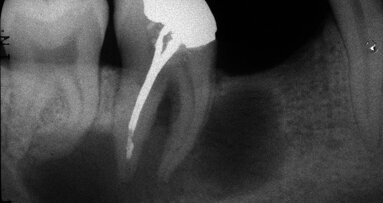

Fig. 2 : Contrôle radiographique en vue d’évaluer l’axe de délogement de la reconstitution corono-radiculaire, ce qui a permis de corriger l’angle de coupe.

D’un point de vue pratique, la première étape consiste à réduire les dimensions du tenon s’il occupe une grande partie de la structure coronaire, de préférence en lui donnant une forme cylindrique similaire à celle d’un tenon préfabriqué. De même, une reconstitution corono-radiculaire coulée ancrée dans plusieurs canaux doit d’abord être sectionnée jusqu’au niveau du plancher de la cavité pulpaire, afin de la traiter comme un ensemble de tenons unitaires, ce qui diminue le degré de rétention global du système. La réduction du tenon doit être effectuée avec des fraises en carbure spécialement conçues pour découper le métal, sous une irrigation abondante. Les évaluations cliniques et radiographies préliminaires sont essentielles pour planifier l’angle de coupe. La procédure doit être fréquemment vérifiée et, si nécessaire, il convient d’effectuer des contrôles radiographiques avant qu’une quantité excessive de dentine ne soit sacrifiée (Figs. 1–3).